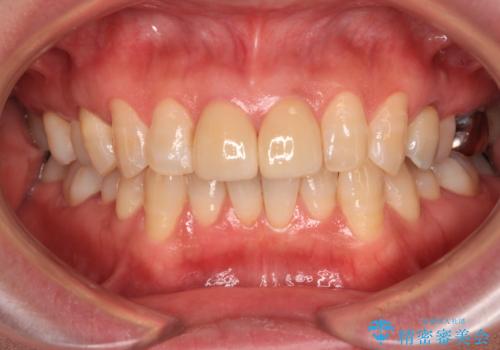

- つぎはぎのある前歯のセラミックの色合いが気になるとのことで来院された患者様です。

グレーの色が透けて見える気がする点が気になっていらっしゃり、やや黄色みのある色を希望されていました。

仮歯に置き換えた後にオールセラミッククラウンにて補綴治療を行うこととしました。

統一感のあるきれいな色調となり、患者様には大変満足していただきました。